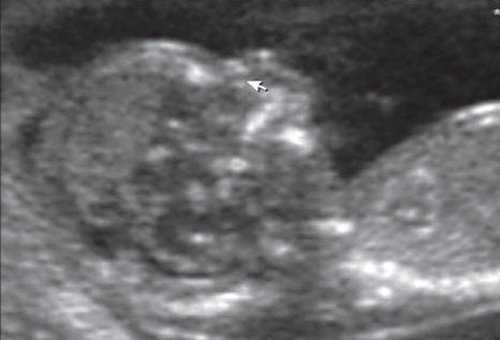

(Слева) УЗИ плода в III триместре, поперечная плоскость, косой срез. Околоплодные воды отсутствуют, определяются увеличенные гиперэхогенные почки.

(Справа) Тот же плод. УЗИ головного мозга. Определяются признаки мальформации Денди-Уокера: расхождение полушарий мозжечка, отсутствие червя, наличие крупной кисты в ЗЧЯ и вентрикуломегалия. Несмотря на то что характерной находкой для синдрома Меккеля-Грубера является затылочное энцефалоцеле, возможны и другие аномалии ЦНС.